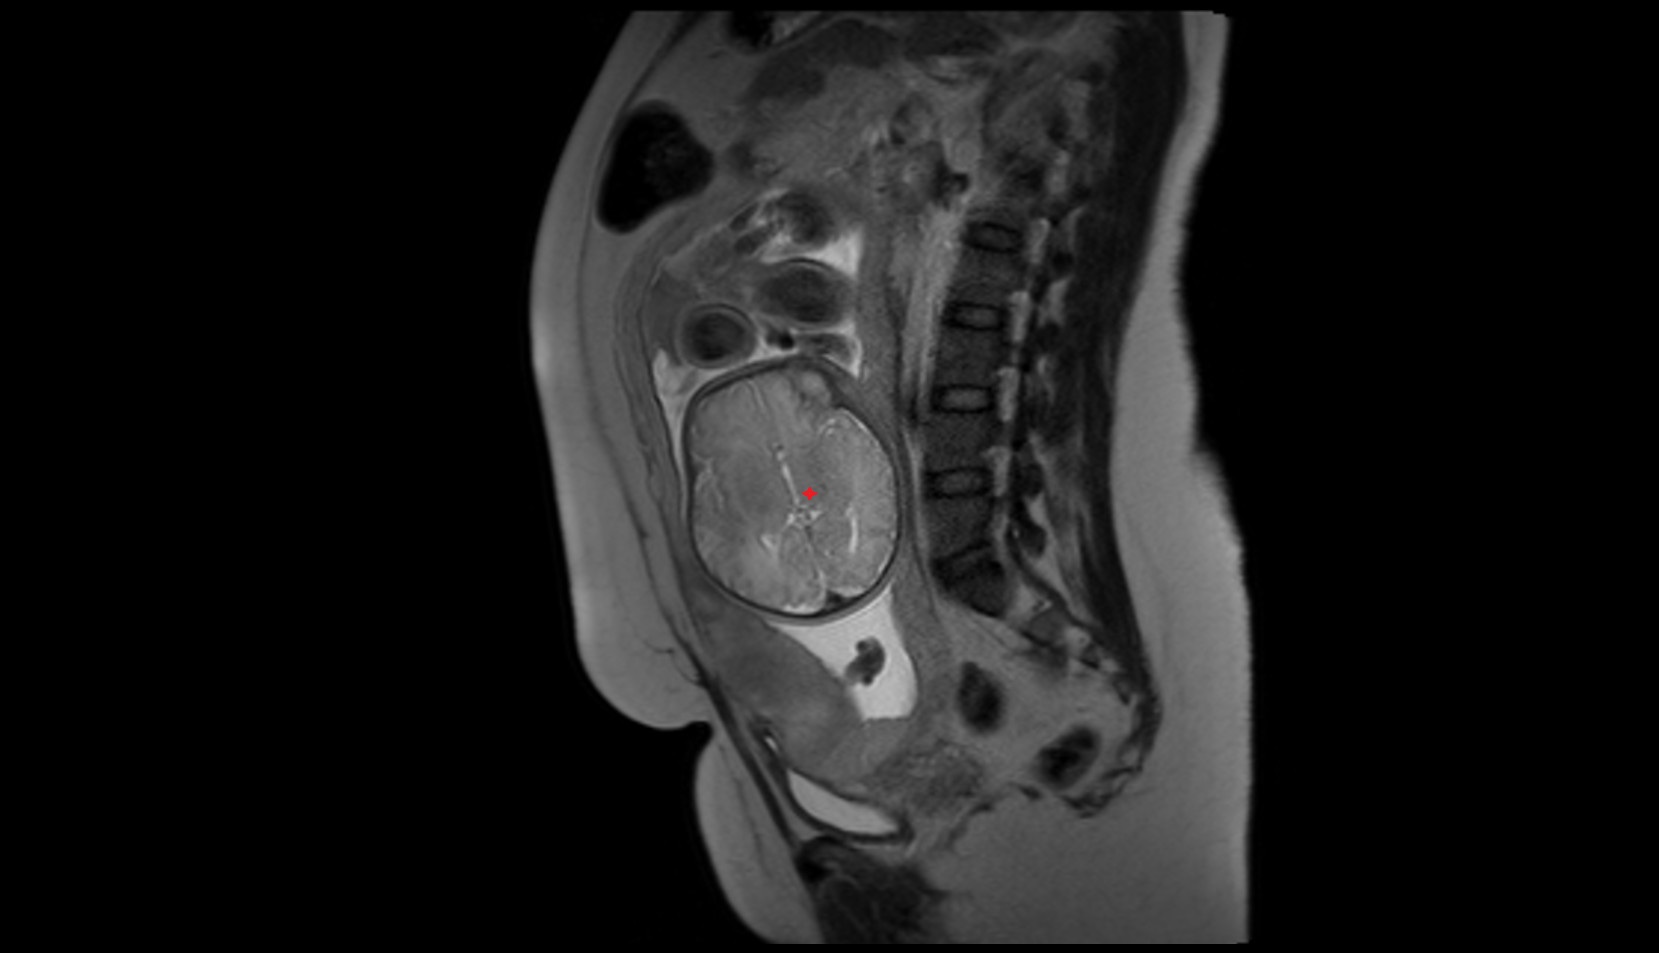

- Placenta

- Uterus (pregnancy)

- Amniotic fluid

- Umbilical cord

- Urinary Bladder in Pregnancy

- Cervix in Pregnancy

- Vagina in Pregnancy

- Fundus of uterus in pregnancy

- Fetal brain

- Fetal caudate nucleus

- Fetal thalamus

- Fetal pons

- Fetal cerebellum